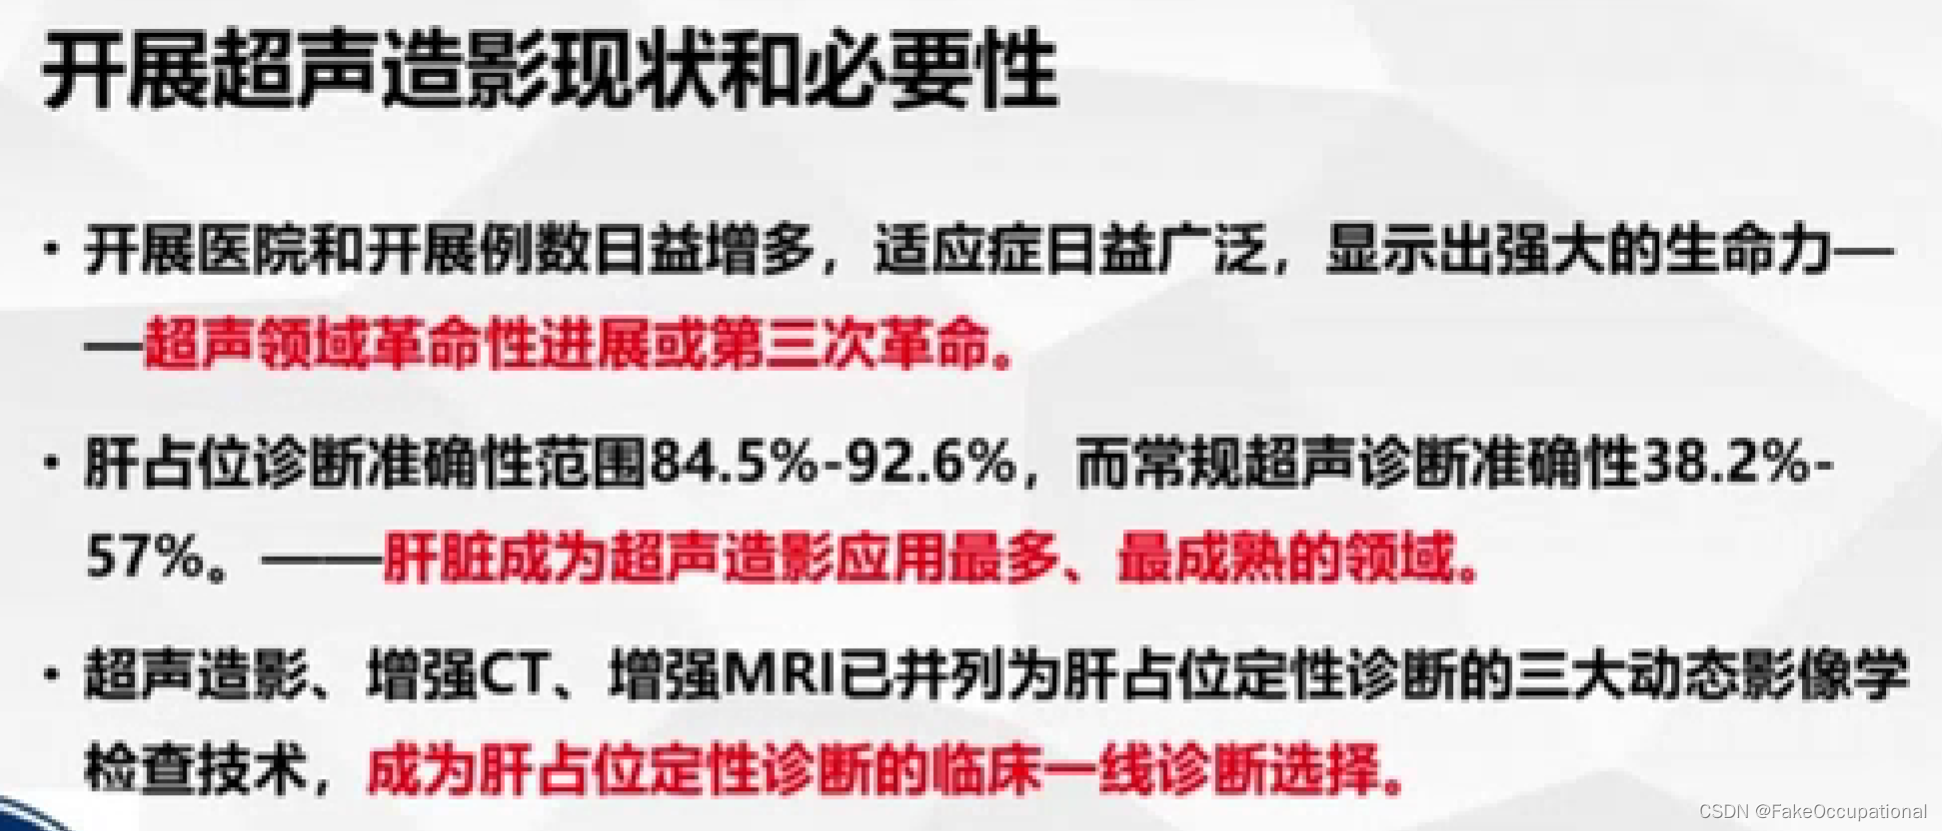

2.超声造影

- 超声更多起一个筛查的作用,定性需要造影或者其他设备的辅助